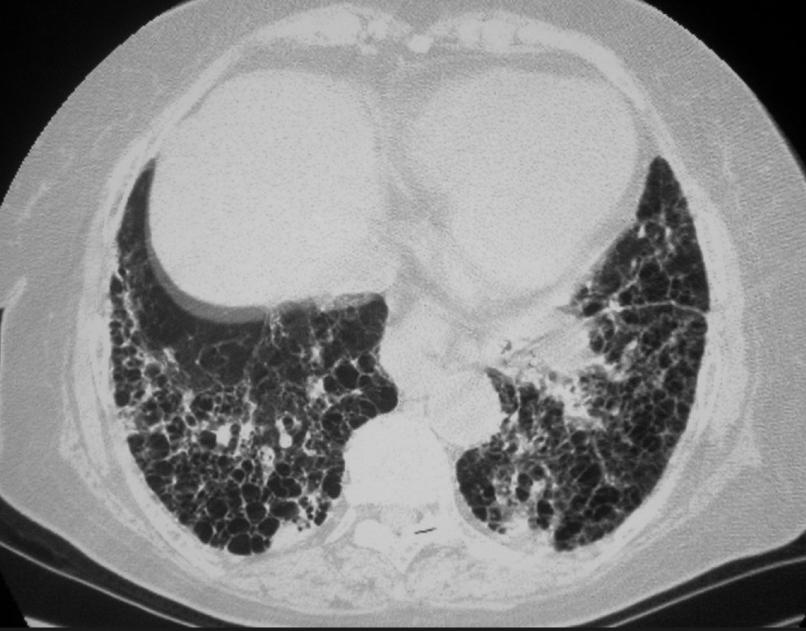

一个奇效古方,名气不大,却是肺纤维化专方 每一次呼吸都变得费力,持续的、撕心裂肺的干咳,却咳不出什么东西;稍稍走几步路就喘不上气,必须停下来大口呼吸;嘴唇和指甲不知不觉中泛出青紫色。感觉自己的肺逐渐干涸、变成失去弹性的海绵。 肺纤维化,在中医理论核心病机在于 “气虚血瘀,络脉痹阻,痰瘀互结,肺络成癥”。简单来说,就是肺气长期亏虚,失去推动力,导致血液和津液运行不畅。血停则为瘀,津停则为痰,痰和瘀像胶水一样黏滞,最终堵塞、痹阻了肺部络脉。络脉不通,气血无法濡养肺组织,肺体失养而逐渐干瘪、僵硬、纤维化。 在中医的宝库中,有一个方子,名气虽不显赫,但其组方思路却精准扣住了肺纤维化的核心病机 —— 它就是 “益气通络消癥汤”。 方解: 全方仅八味药,却环环相扣:以黄芪补气为发动机,以丹参、三七活血消癥为主力军,以浙贝母化痰散结为协同,以地龙通络平喘为尖兵,再以麦冬、甘草滋阴调和为后勤保障。共奏 益气活血、化瘀通络、消癥散结 之效。 案例分享: 曾诊治一位68岁的男性肺纤维化患者,确诊两年,曾使用激素治疗,副作用明显后寻求中医。 来时面色发黑,口唇发紫,行走不足百米即喘促不止,干咳连连,夜间尤甚,严重影响睡眠,舌质紫暗,苔少,脉细涩。西医CT提示双下肺网格状、蜂窝状改变。 辨证属 “气虚血瘀,络阻肺痿”。 以 “益气通络消癥汤” 为底方:重用黄芪、丹参,加莪术助活血消癥,加山茱萸、五味子益肾纳气、收敛肺气,以防咳得厉害耗伤肺气。 服药一月后复诊,患者自述咳嗽频率减少,夜间能安睡数小时,散步时气促感略有减轻。 坚持调治半年后,患者精神状态明显好转,日常室内活动已无明显气促,复查肺部CT提示纤维化病灶范围未见明显进展。目前仍在门诊间断调理,稳定病情,提高生活质量。 注:本文所述方药及案例旨在分享中医学术思路,不做调理依据,任何调理都必须在专业指导下进行,切勿自行试药!